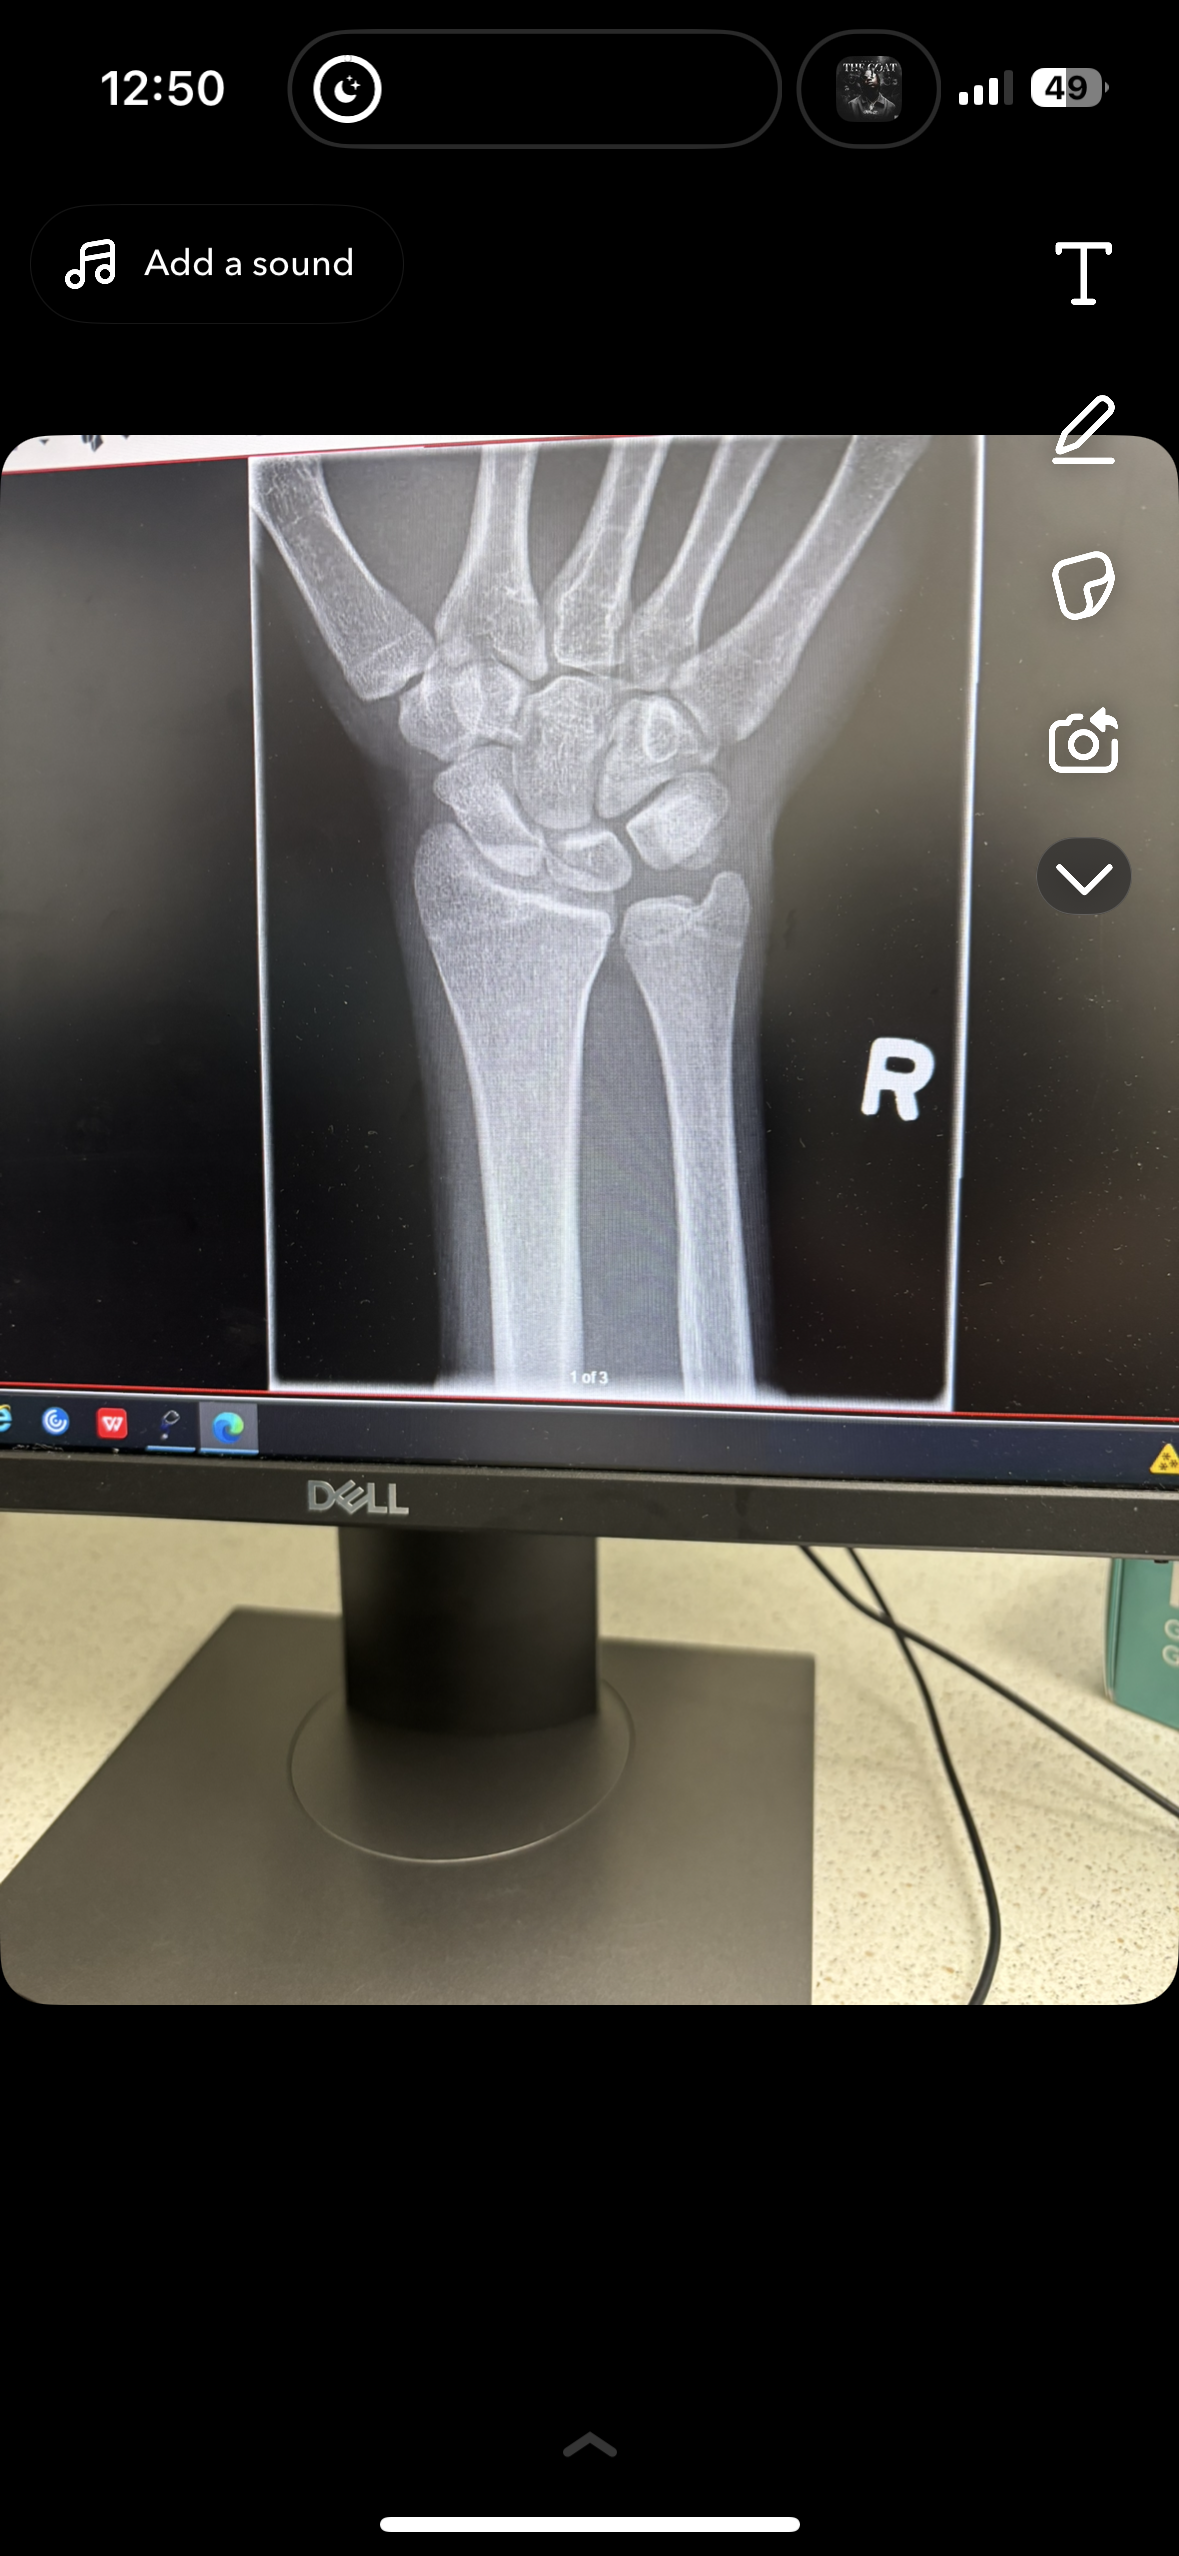

Bone plates gh and height

are my wrist bone plates closed ? I’m 18 and do you think any of my other plates would be open, would taking gh infinigrib and an ai benefit me at this point. Or would it cause harm to me from side affects I hear if you take gh after closure it may just harm you more then it helps u and for me I’m not for sure if all my plates are closed should I hop on?

Yours appear to be closed to me.

they’re closed but u should get ur knees checked, they are your last hope, if they’re open u might have a small window of growth left

Should I get my spine too I heard their growth plates there too, I’m prolly tell my doctor I got pain and just get an X-ray for both, is there any harm in trying to take it for a few months and if I don’t notice height growth just hopping off ?